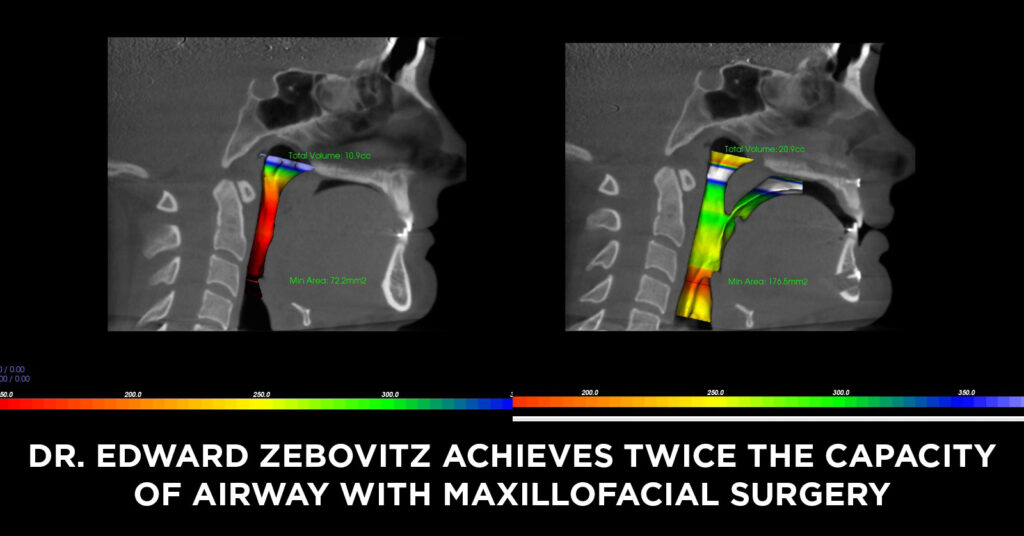

AIRWAY AND BREATHING BENEFITS

In most jaw surgery cases we see a significant improvement in airway volume = more oxygen delivered throughout the night = feeling more rested, increased energy, and better brain function during the day.

Even if you’re not experiencing any sleep apnea symptoms right now, they may develop in the future due to muscles getting weaker, weight gain, or other factors.

Airway assessment